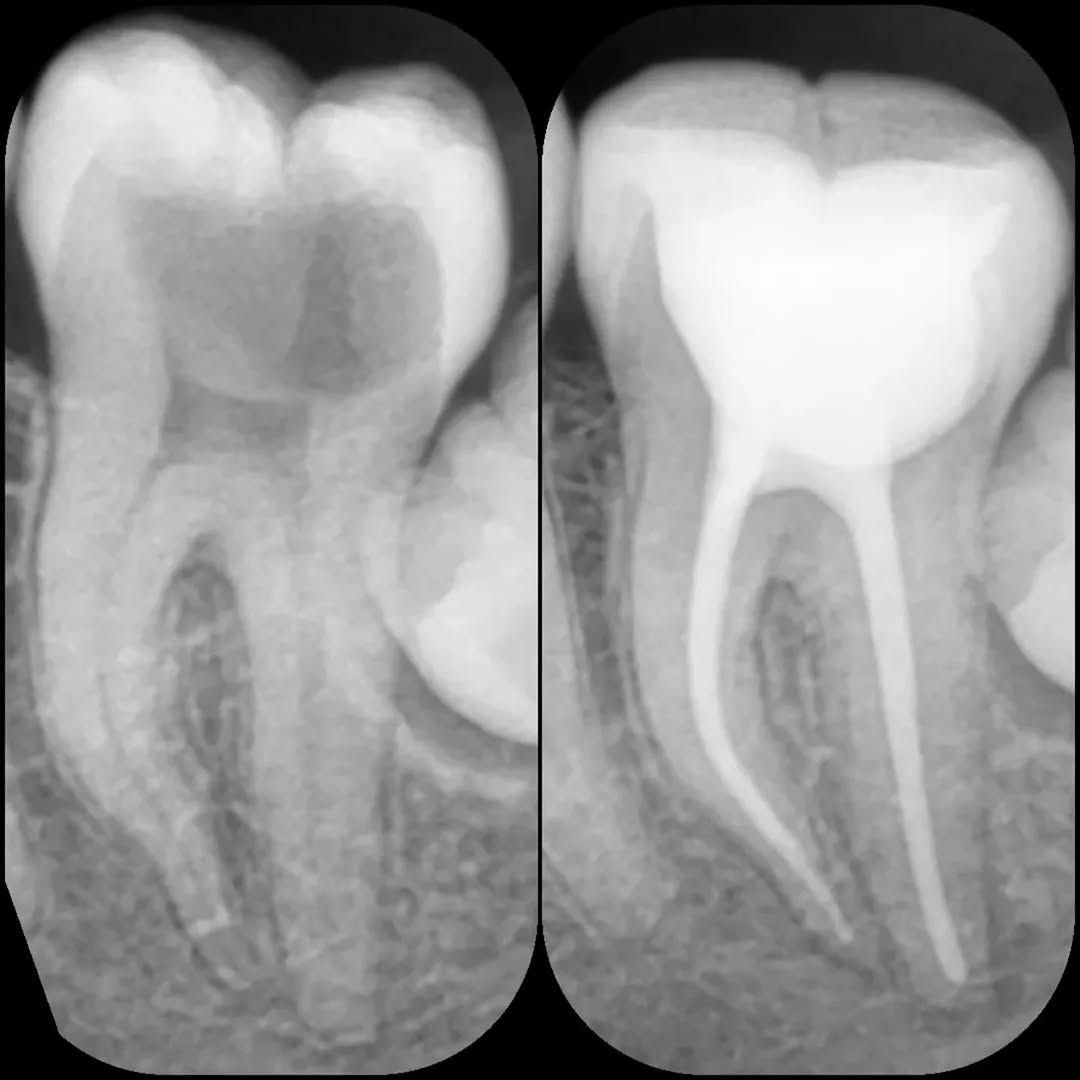

- درمان ریشه (عصبکشی)